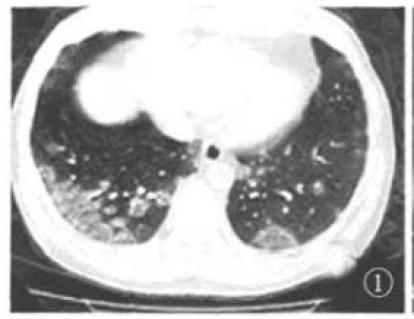

典型的新冠肺炎影像学并不难,诊断的关键是:

早期出现小斑片或间质性改变,常有磨玻璃阴影;

病灶主要位于胸膜下。随着病情进展,病灶常为双肺多发。

随着病情进展,CT失去特异性,不容易鉴别与一般的肺炎。

特别是后期变成“白肺”,没有之前的影像学做对比,更是没办法做出准确的诊断。